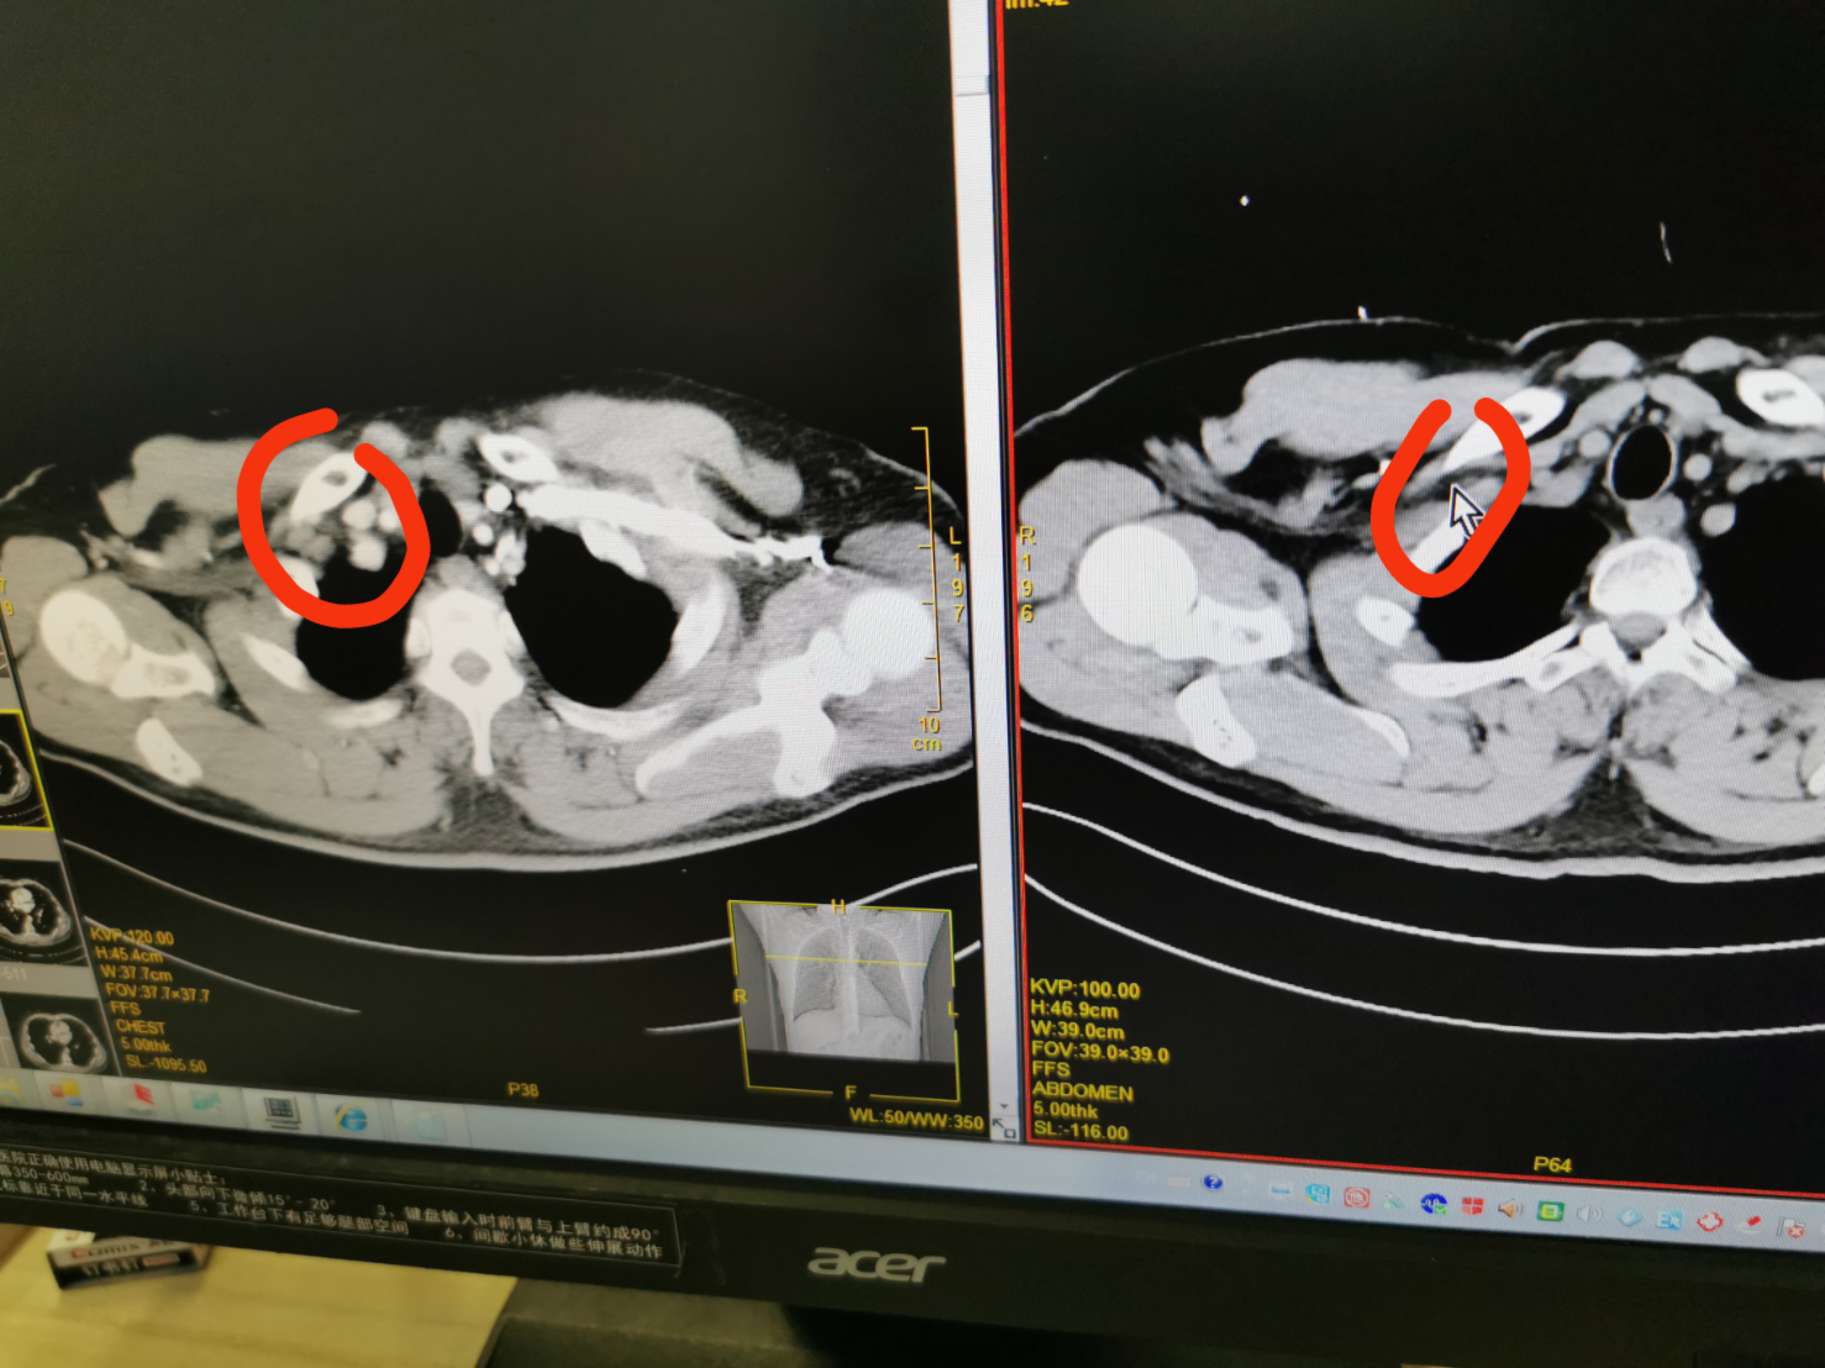

6.5完成了四化三十放,6.16复查,整体算大pr,不过没有通过放化疗cr还是有一些遗憾,6.18赶在14天内上了第一次i药,毕竟14天内的亚组受益惊人,可能多方面的原因,14天内可以上代表同步放化疗耐受,同时放疗的增敏效果更明显,希望放疗的余威和i药可以双剑合璧,干掉小癌。最后吐槽下,我确诊时报ct结果的影像科,明明这么多淋巴结转移,都没报,要是做了手术不得哭死。收藏

短径